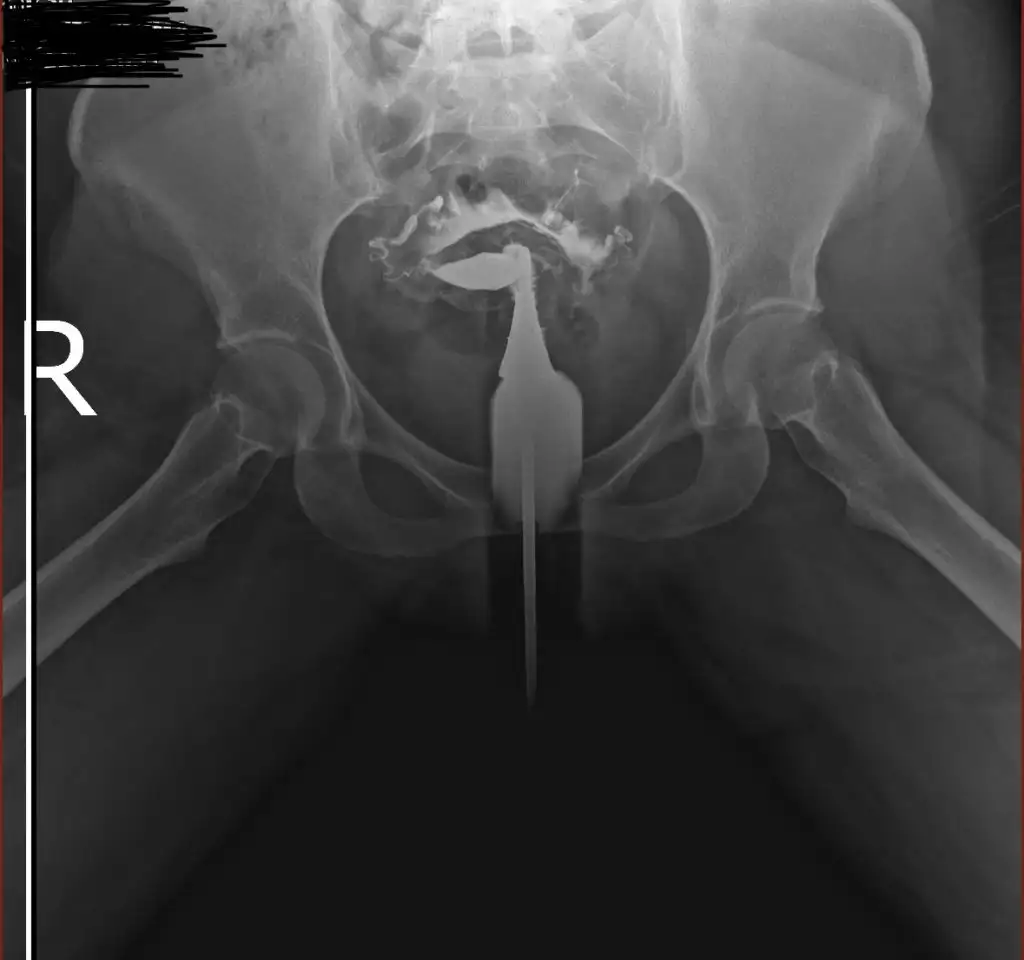

İlaç karın boşluğuna yayılmış tüplerin açık olduğu anlamına geliyor. Farklı bi görüntü var mı tek taraflı gibi duruyor gibi geldi banaHerkese merhaba bana da yardımcı olursanız çok sevinirim. Dün hsg çektirdim doktorum tüplerimin açık olduğunu söyledi. Fakat ben görüntülerden bir şey anlamadım. Bilgisi olan yorumlarsa çok sevinirim görüntüleri yüklüyorum.

Sadece bu görüntüleri yüklemişlerdi e nabıza maalesef teşekkür ederim cevabınız için şüpheye düştüm görüntüden anlamayıncaİlaç karın boşluğuna yayılmış tüplerin açık olduğu anlamına geliyor. Farklı bi görüntü var mı tek taraflı gibi duruyor gibi geldi bana

Açık dedi doktor raporda da açık yazıyordu. Benim de görüntüm böyleydi karın boşluğuna ilaç yayılmış şekildePeki sizin tüpleriniz açık mı çıktı acaba benim görüntülerden bir şey anladınız mı

Anladım teşekkür ederim bende rapor olmayınca kafam karışmıştıAçık dedi doktor raporda da açık yazıyordu. Benim de görüntüm böyleydi karın boşluğuna ilaç yayılmış şekilde

Normal görünüyor rapora göreMerhaba kızlar film sonucum bu. Bilenler bakabilir mi?